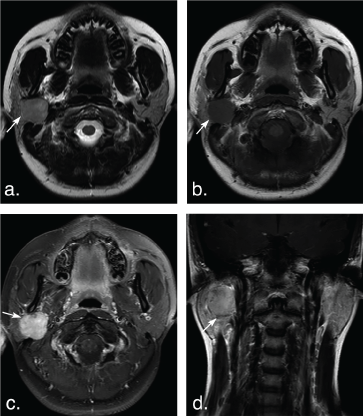

Figure 5: A 63-year-old man with Warthin tumors in the deep lobe of the left parotid gland. T2 weighted image (a) and T1 weighted image (b) show a well-defined, lobulated, heterogonous tumor. Lesion with irregular cystic area (arrowheads) and solid nodule (arrows). The solid portion of the tumor shows hypoinentse signal on T2 weighted and T1 weighted MR images, and mild enhancement (arrow) on axial contrast-enhanced fat-suppressed T1 weighted image (c) and coronal non-fat suppressed T1 weighted image (d) (arrows). View Figure 5

Figure 6: A 74-year-old man with multiple Warthin tumors in the superficial lobe of the right parotid gland and the deep lobe of the left parotid gland. Axial T2 weighted image (a) and axial T1 weighted image (b) show multiple, well-defined, ovoid tumors in bilateral parotid (arrows). The tumors show hypointense signal on T2 weighted and T1 weighted MR images, and mild enhancement (arrow) on axial contrast-enhanced fat-suppressed T1 weighted image (c) and coronal non-fat suppressed T1 weighted image (d) (arrows). View Figure 6

The solid portion of tumors in 7 of 9 BCAs (77.78%) and 8 of 62 PAs (12.90%) were hypointense on T2 weighted imaging. Two of 9 BCAs (22.22%) and 43 of 62 PAs (69.36%) showed mixed hyper- and hypointense, and 11 of 62 PAs (11.74%) showed hyperintense on T2 weighted imaging (Figure 4 and Figure 5). No lesion has hyperintense signal in BCAs and WTs on T2 weighted imaging (Figure 1, Figure 2, Figure 3, Figure 4, Figure 5 and Figure 6). There was significant difference between BCAs and PAs (P < 0.001).

Enhancement of tumor solid portion on the delayed phase of fat-suppressed contrast-enhanced T1 weighted imaging was significantly different between BCAs and WTs (P < 0.001). All lesions of BCAs and 43 of 62 (69.35%) PAs showed marked enhancement, while only 3 in 58 WTs were markedly enhanced (Figure 1, Figure 2, Figure 3, Figure 4, Figure 5 and Figure 6). No significant difference was found between BCAs and PAs (P = 0.0124).